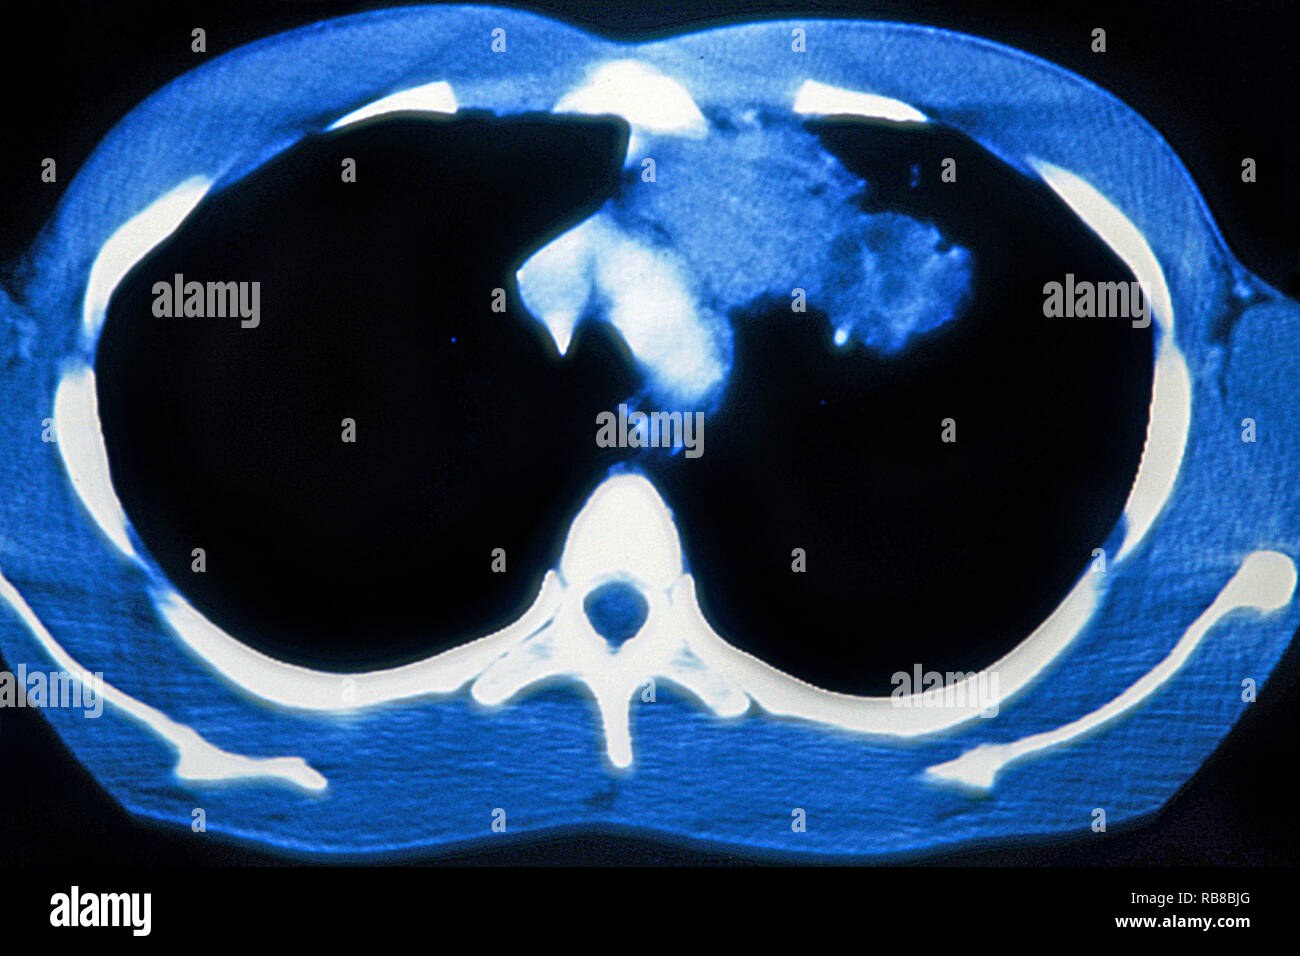

RM2RF8HPX–Pneumonie du poumon droit (infection respiratoire aiguë) révélée par une radiographie thoracique frontale.

RM2RF8HR9–Pneumonie du poumon droit (infection respiratoire aiguë) révélée par une radiographie thoracique frontale.

RM2RF8HPN–Pneumonie du poumon droit (infection respiratoire aiguë) révélée par une radiographie thoracique frontale.